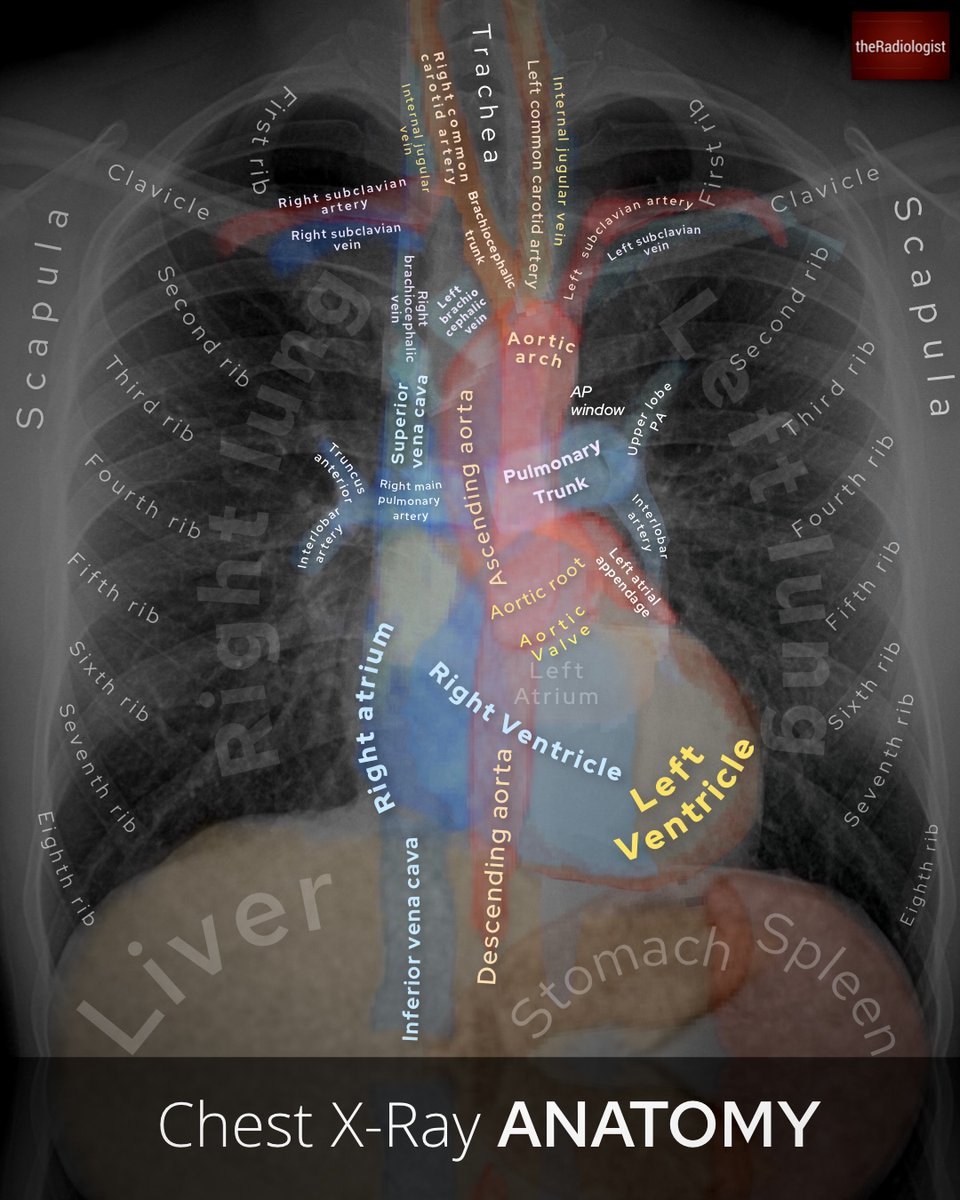

Chest X-Ray anatomy and review areas